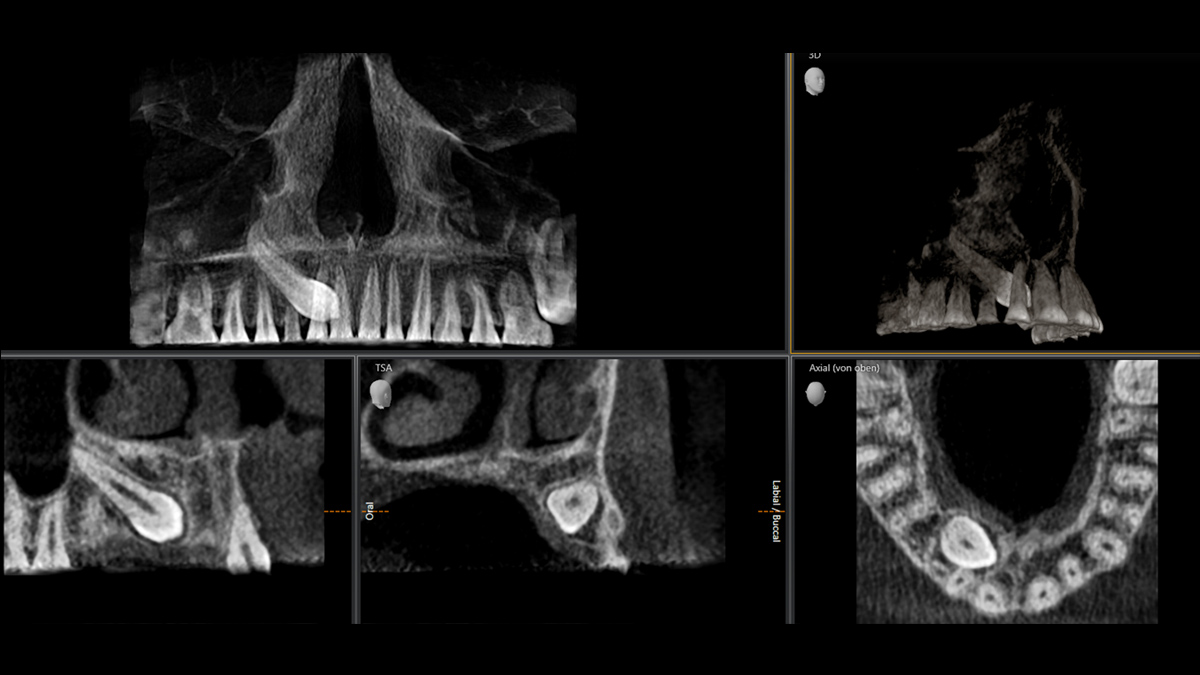

La tecnología 3D se está estableciendo cada vez más en los consultorios dentales en todo el mundo. Para diagnósticos más precisos y explicaciones del tratamiento, los rayos X en 3D ofrecen varias ventajas. Ya sea para dientes superpuestos, recorridos inesperados de los canales de los nervios, raíces ocultas o anomalías de las articulaciones temporomandibulares, las imágenes en 3D tienen un valor inestimable para un gran número de diagnósticos.

Orthophos SL 3D ofrece una gran variedad de opciones para satisfacer estas necesidades: diferentes tamaños de volumen donde elegir, modos HD/SD/Dosis bajas de radiación y un software inteligente e intuitivo para aprovechar al máximo las imágenes obtenidas y vincularlas directamente al tratamiento.

Galería de muestra de imágenes panorámicas 3D

Orthophos SL 3D en la práctica